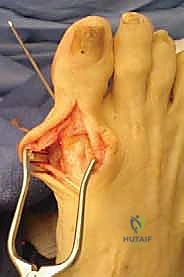

2. الشق الجراحي والوصول للمفصل

يقوم الدكتور هطيف بعمل شق جراحي دقيق أعلى المفصل (Dorsal Approach) بطول يتراوح بين 4 إلى 6 سم، مع الحرص الشديد على حماية الأوتار والأعصاب الحسية المحيطة بالمنطقة.

يتم إغلاق الأنسجة والجلد بخياطة تجميلية دقيقة لتقليل الندبات، ثم تُلف القدم بضمادات معقمة واقية.